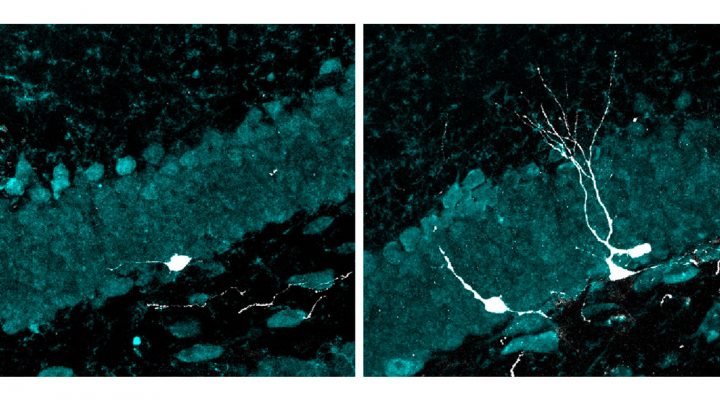

“Esas nuevas neuronas mostraron, además, un desarrollo más avanzado que las de los animales del grupo control: crecieron más, formaron dendritas y axones más complejos (los cables de entrada y salida de las neuronas) y establecieron conexiones más eficaces con el resto del circuito”, resalta la investigadora del CONICET Mariela Trinchero, autora principal del estudio junto a Magalí Herrero, becaria doctoral del CONICET, ambas integrantes del Instituto de Investigaciones Bioquímicas de Buenos Aires (IIBBA, CONICET-FIL) y del Laboratorio de Plasticidad Neuronal que lidera Schinder en la Fundación Instituto Leloir (FIL).

Pero no se conocen los mecanismos detrás de esos aparentes beneficios. Para investigar los efectos de la estimulación sensorial a 40 Hz sobre los circuitos neuronales, los equipos de investigación del CONICET y de la FIL trabajaron con ratones envejecidos que fueron expuestos diariamente a luz LED intermitente y a un tono auditivo de alta frecuencia a través de un parlante, que oscilaban a 40 ciclos por segundo. Luego, analizaron el hipocampo, la única región del cerebro que tiene la particularidad de generar neuronas a lo largo de toda la vida. Ese proceso, conocido como neurogénesis adulta, disminuye drásticamente con la edad.